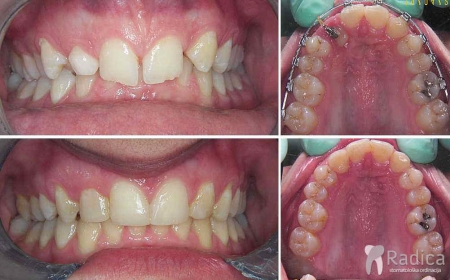

Primjeri fiksne ortodontske terapije dubokog zagriza:

Primjer terapije kod dubokog zagriza: